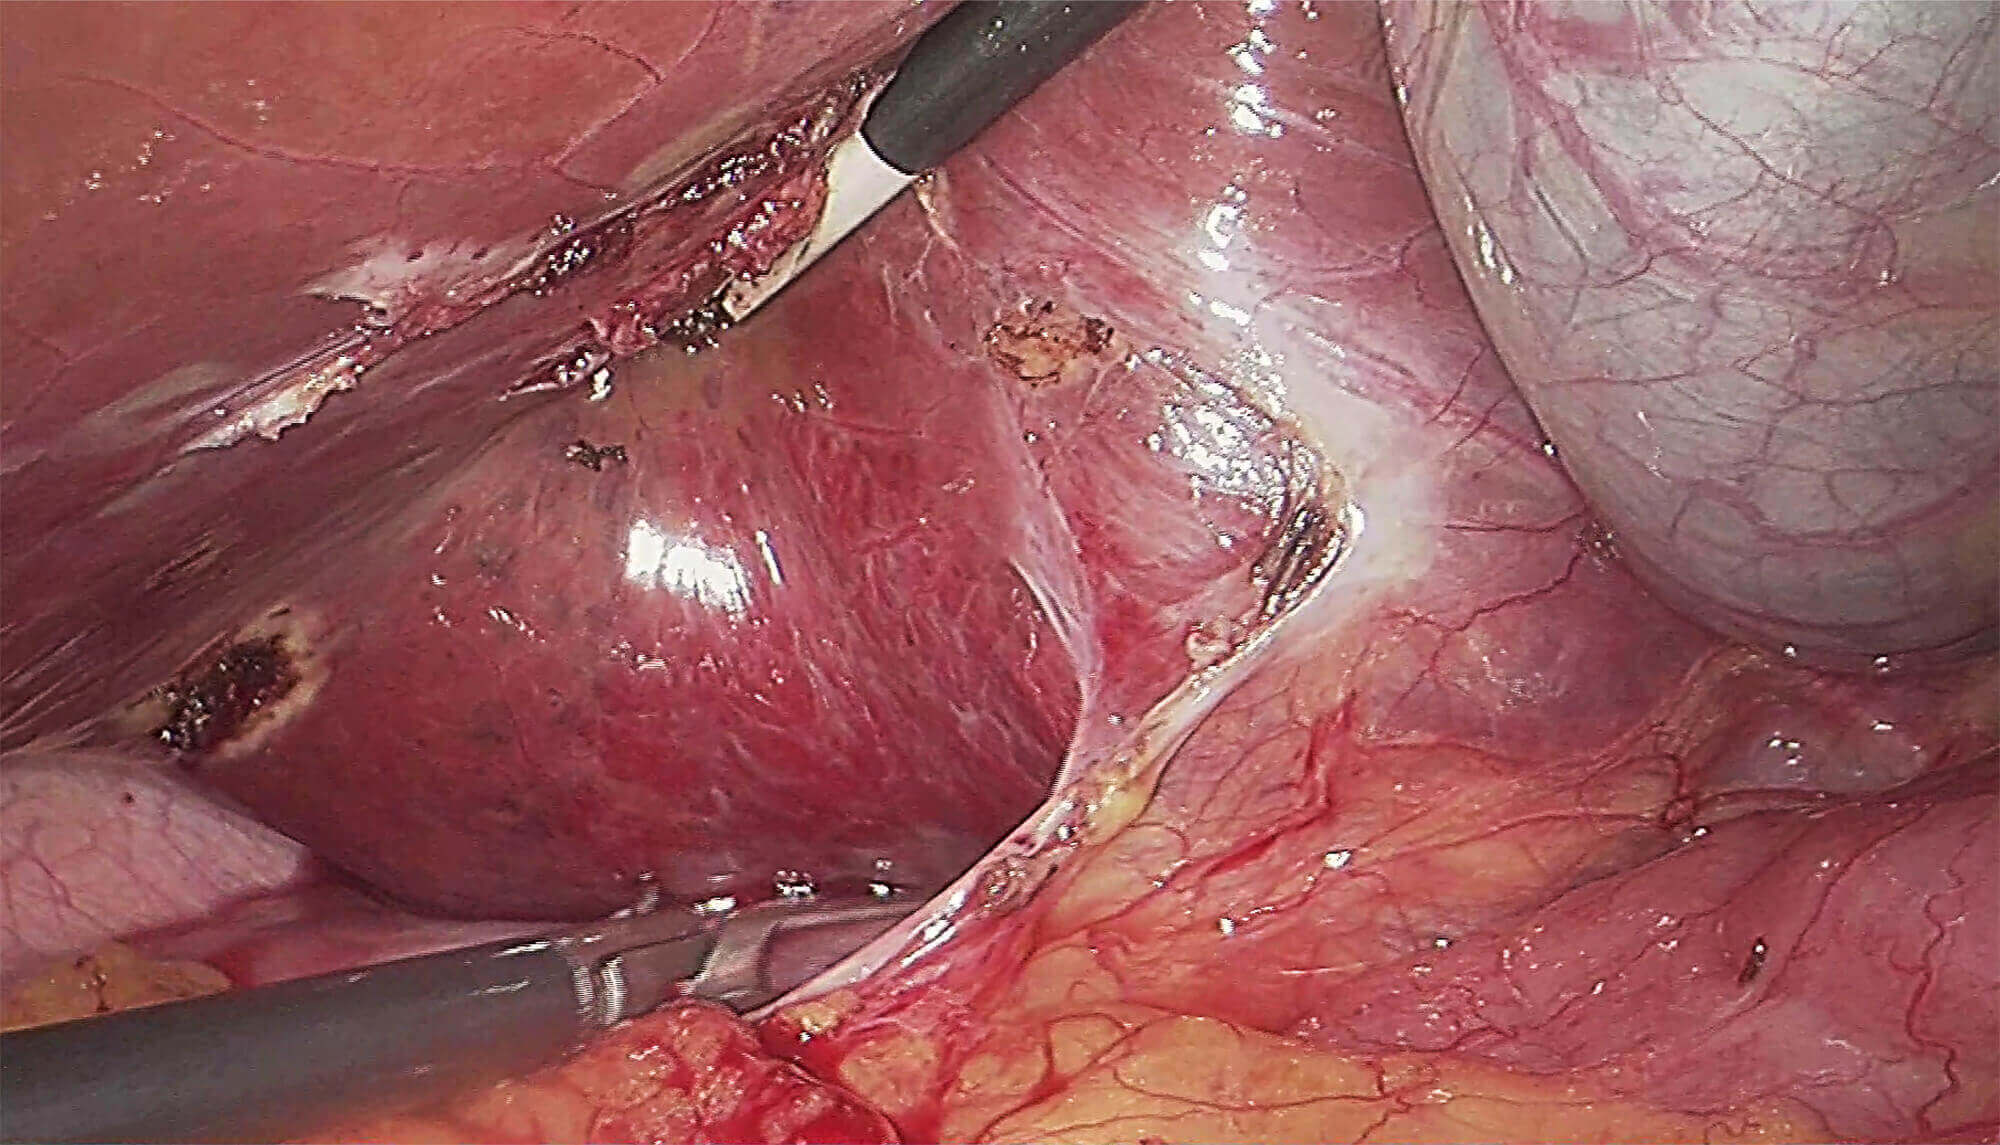

清晰的腔镜视野

采用3片CMOS图像传感器,输出1920*1080P、60FPS全高清数字信号,提供稳定的腔镜视野,给予术者极佳的视觉体验,让手术更轻松,更精细!

• 腹腔镜

高清晰度

采用蓝宝石镜面设计

高密封设计,提高耐用性

可高温高压或低温等离子灭菌

直径5mm/10mm、视角0°/30°可选